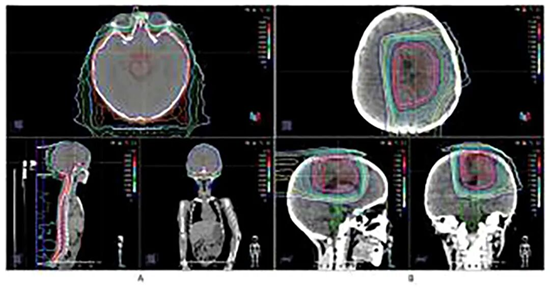

质子治疗计划及剂量分布。(A)全脑全脊髓照射(CSI),剂量36Gy,分20次照射。(B)局部加强照射,剂量18Gy,分10次照射(总剂量54Gy)。

在为患儿进行了大范围的安全手术切除后,治疗团队选择了医院的质子治疗(PBT)进行术后辅助放疗。质子治疗凭借其独特的“布拉格峰”物理优势,能够将放射剂量精准集中在肿瘤区域,同时最大限度地保护周围的正常脑组织。这一步不仅是精准的初步治疗,更是一次极具远见的“布局”——通过减少对健康组织的损伤,为后续可能需要的再次放疗保留了宝贵的“窗口期”。